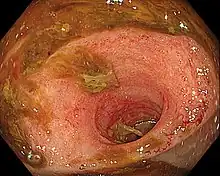

Ileitis caused by capecitabine.

Ileitis is an inflammation of the ileum, a portion of the small intestine. Crohn's disease is the traditional cause of ileitis. Ileitis, however, may be linked to a broad range of illnesses. These comprise a range of illnesses, such as sarcoidosis, amyloidosis, ischemia, neoplasms, spondyloarthropathies, vasculitides, drug-related conditions, and eosinophilic enteritis.[1]